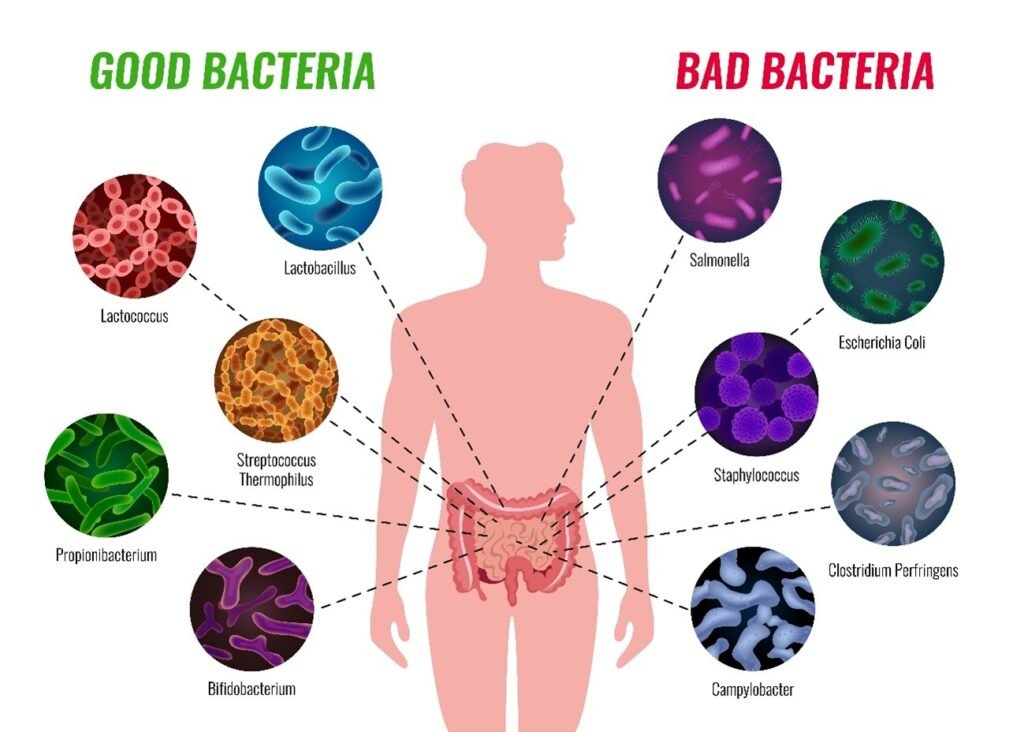

- Oral Microbiome: The ecosystem of microorganisms in the mouth plays a role in oral health. Body shifts of this balance can result in dental caries (cavities) and gum diseases like gingivitis and periodontitis.

- Periodontal Disease and Systemic Effects: Periodontal disease, which is a bacterial infection in the dental plaque, causes inflammation and degradation of gum tissue and bone, which support the teeth. Infections and inflammation of gums may transiently enter the bloodstream (transient bacteremia), distributing bacteria, microbial toxins, and inflammatory mediators to the body.

- Mechanisms of Influence: Mechanisms through which oral infections may have systemic consequences include the translocation of bacteria throughout the body, transmission of bacterial toxins, and systemic inflammation initiated by oral bacteria. These can aggravate chronic inflammation and immune responses that lead to systemic illnesses.